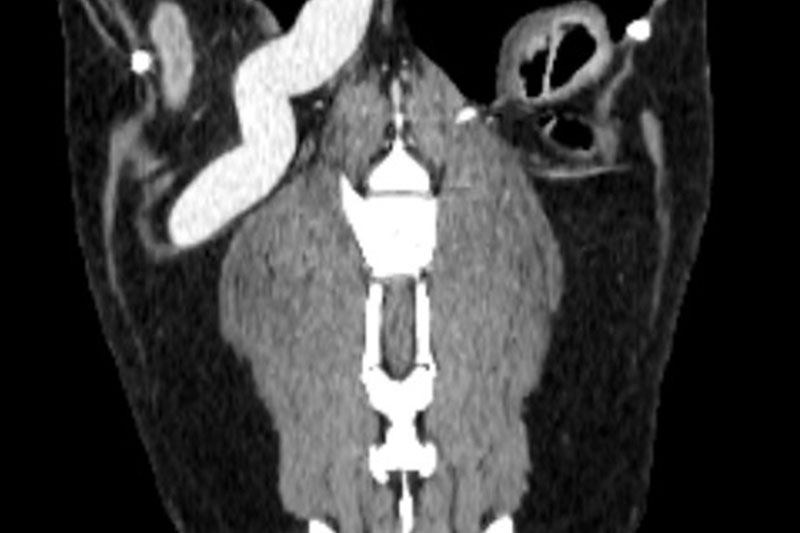

CT (Computed Tomography, 전산화 단층촬영) 검사는 X-ray를 이용해 반려동물의 몸을 여러 각도에서 촬영하고, 이를 컴퓨터로 합성하여 단면 이미지(슬라이스)를 만들어내는 정밀 진단 장비입니다.

사람 병원에서도 널리 사용하는 기술로, 뼈, 장기, 혈관, 종양 등 몸속 구조를 3차원(3D)으로 시각화할 수 있습니다.

| 두부(머리) | 뇌종양, 두개골 골절, 중이염, 치주염, 안와(눈) 질환 등 |

혈관 조영(Angio CT)을 통한 혈관 이상 진단